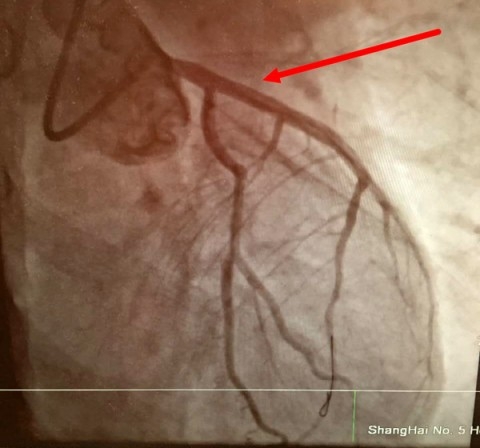

中午12时,持续抢救四小时,患者室颤发作次数有所减少,机不可失,抓住短暂平稳间期立刻手术开通血管,是患者生存唯一可能。徐迎佳主任亲自护送,立刻携带呼吸机、除颤仪、监护仪等设备将黄先生安全迅速转运至放射科介入导管室,风驰电掣展开心脏冠脉造影手术。术中,黄先生再次室颤,又一次抢救除颤复律成功。徐迎佳主任与张高峰主任医师、乔琪主治医师等抓住稍纵即逝的机会,冠脉造影显示前降支近端闭塞,迅速置入支架,手术仅用了20余分钟。